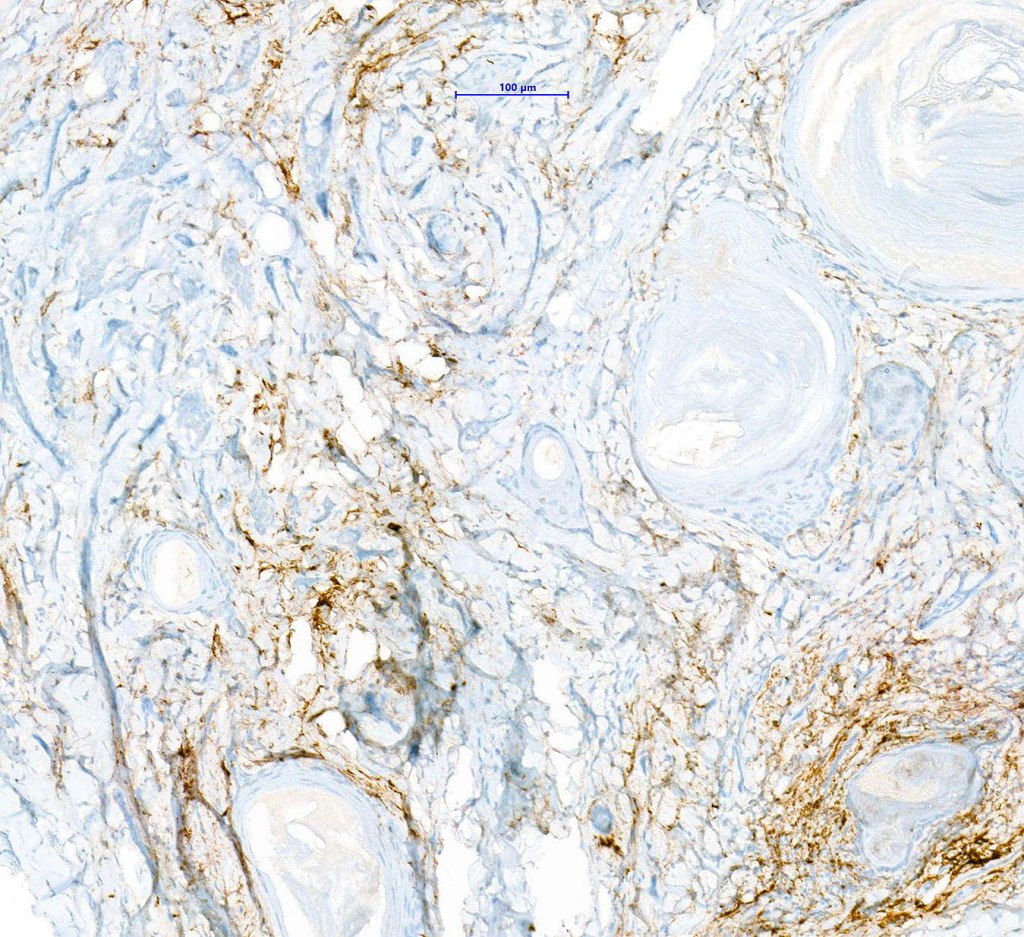

•CK20 highlights Merkel cells

. EMA & CEA show no evidence of ductal differentiation